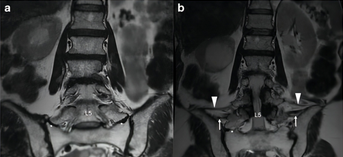

脊柱畸形的定位与计数椎体!